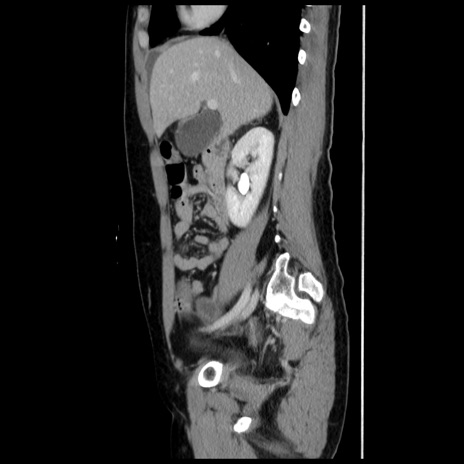

症例10(矢状断像)

【症例】 50歳代女性

【主訴】 腹痛

【現病歴】前日生レバーを食べた。今朝に排便あり。 昼前に突然発症の腹痛を生じ、当院救急外来を受診した。

【既往歴】 子宮筋腫にてで子宮全摘後

【身体所見】 意識清明、腹部:平坦、軟、下腹部やや左を中心に圧痛・反跳痛あり、筋性防御あり

【データ】WBC 7800、CRP 0.07